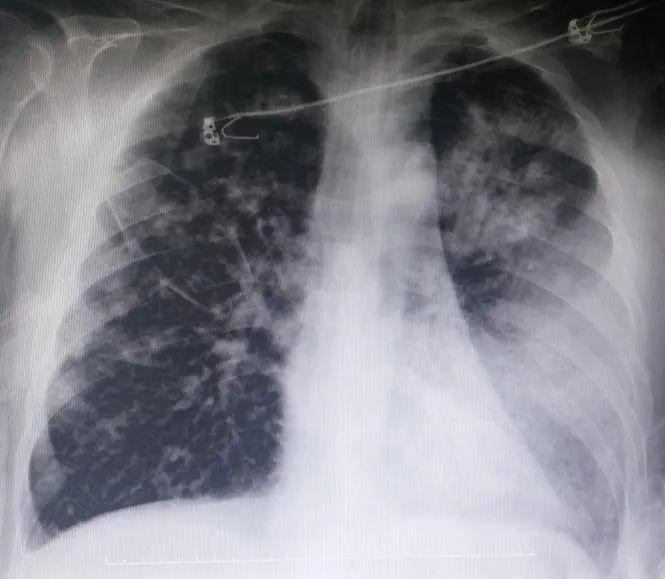

ICU内检查发现:CRP:137mg/dL,白细胞33400/mm²,中性粒细胞32% 。因此由头孢曲松转为使用美罗培南联合利奈唑胺进行治疗,次日行胸部CT检查可见周围及部分空洞结节、浸润、纵隔淋巴结肿大(最大直径1 cm)、双侧胸腔积液及供血血管征(图3)。由于胸腔积液很少,所以没有进行胸腔穿刺术。

图2 ICU胸片